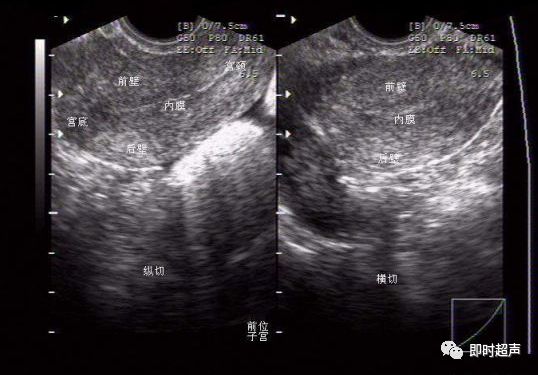

1.阴超最大的难度是方向问题,要非常清楚探头的位置和方向,以探头上标向上纵切子宫:左为腹侧,右为背侧,近场为宫颈,远场为宫底。

子宫前后位的判断主要看宫底是靠近腹侧(前位)还是背侧(后位),如果纵切时图象怎么打也是个横切的图象,那子宫就是水平位,因为子宫与声束平行,这时要左或右侧偏一点,使声束方向改变。探头横切时,主要看探头在盆腔的位置,因为阴超视野较小。探头偏向左显示的就是左侧盆腔,反之亦然。如果习惯了阴超的方向,其实和经腹部看一个道理,慢慢体会就行。

A显示阴超纵切,子宫呈前倾/前屈,并在监视器上显示。图像由声束进入人体后旋转90度而得。声束顶端(狭窄部分)在探头表面,经90度旋转后出现在图像的上方。腹部超声和阴超都可显示前腹壁(a)。B 横切前倾/前屈的子宫,图像见上。由探头逆时针旋转90度而得。同样由声束进入人体后旋转90度而得。子宫右侧(r)出现在图像左侧。